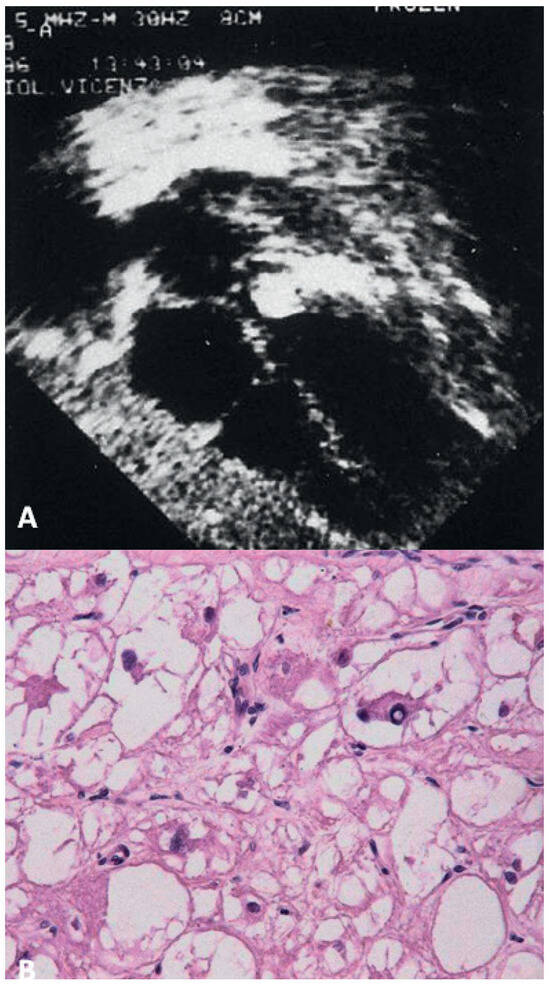

Papillary fibroelastoma

- Basso, C.; Bottio, T.; Valente, M.; Bonato, R.; Casarotto, D.; Thiene, G. Primary cardiac valve tumours. Heart 2003, 89, 1259–1260. [Google Scholar] [CrossRef]

- Valente, M.; Basso, C.; Thiene, G.; Bressan, M.; Stritoni, P.; Cocco, P.; Fasoli, G. Fibroelastic papilloma: a not-so-benign cardiac tumor. Cardiovasc Pathol. 1992, 1, 161–166. [Google Scholar] [CrossRef] [PubMed]

- Klarich, K.W.; Enriquez-Sarano, M.; Gura, G.M.; Edwards, W.D.; Tajik, A.J.; Seward, J.B. Papillary fibroelastoma: echocardiographic characteristics for diagnosis and pathologic correlation. J Am Coll Cardiol. 1997, 30, 784–790. [Google Scholar] [CrossRef]

- Bottio, T.; Pittarello, D.; Bonato, R.; Thiene, G.; Gerosa, G.; Casarotto, D.; Basso, C. Echocardiographic diagnosis of aortic valve papillary fibroelastoma. Tex Heart Inst J. 2004, 322–323. [Google Scholar]